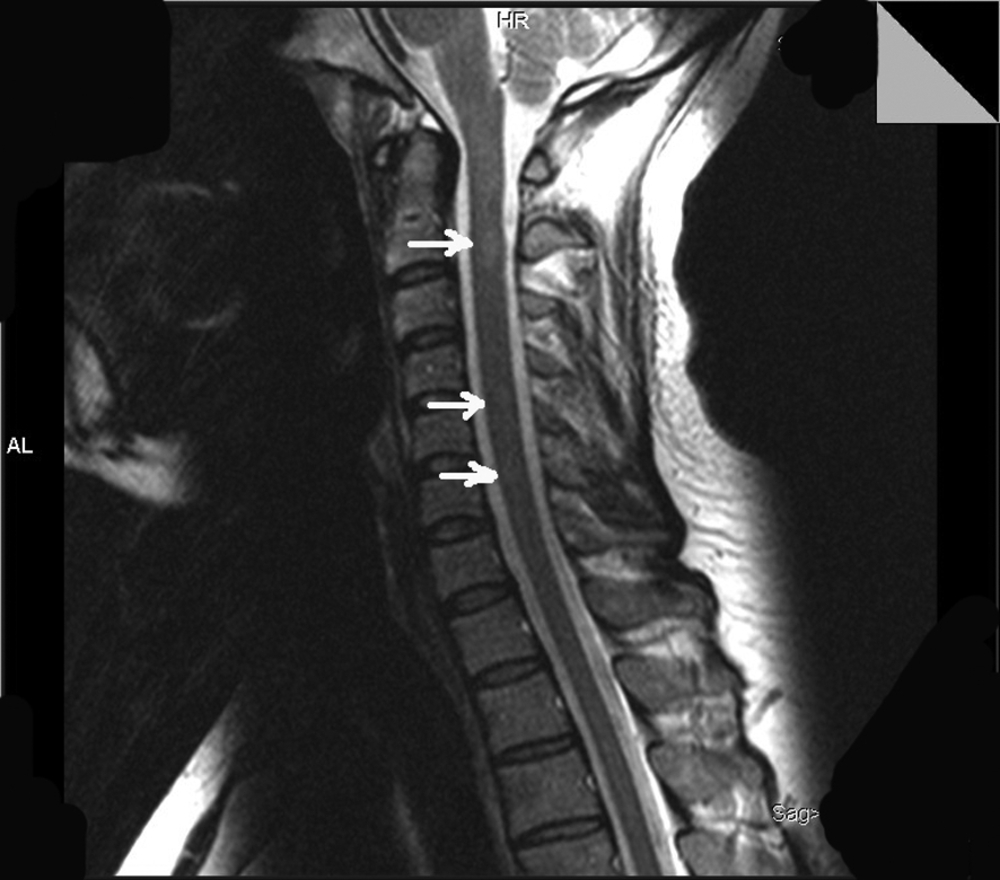

На уровне сегмента С2 определялись 2 интрамедуллярных очага без четких контуров, слабогиперинтенсивные на Т2-ВИ и изоинтенсивные на Т1-ВИ, размерами 4×6 и 4×7 мм. Не исключалось наличие аналогичного очага на уровне сегментов С4-С5 и С5-С6 шейного отдела спинного мозга (рис. 2).

В большинстве случаев ССМ являются симптоматическими, и в их основе лежат очаги в спинном мозге, обусловленные каким-либо первичным заболеванием — инфекцией [24-26], опухолью [27], артериовенозной мальформацией [28], сирингомиелией [16], острым рассеянным энцефаломиелитом [29], вертебральной патологией [28], ятрогенией [125] и т.д. [10, 30-35]. Напомним, что у наблюдаемого больного обнаруживались очаги демиелинизации на уровне сегментов С2, С4, С5, С6 шейного отдела спинного мозга, и именно эти очаги могли служить причиной возникновения миоклонических подергиваний сегментарного характера (см. рис. 2).

Описанное нами наблюдение демонстрирует яркую картину ССМ при РС. Отсутствие эпилептической активности на ЭЭГ, наличие разрядов в мышцах левой руки (сегмент С7), вовлечение в гиперкинез мышц левой верхней конечности, иннервация которых обеспечивается 3-4 соседними сегментами, и, наконец, регистрация очагов демиелинизации в спинном мозге, а именно на уровне сегментов С2, С4, С5, С6 шейного отдела, — все это подтверждает спинальный сегментарный характер миоклоний. Причиной возникновения ССМ, скорее всего, послужили очаги демиелинизации в спинном мозге. Исчезновение гиперкинеза после терапии гормонами укрепляет наше предположение о генезе насильственных движений.